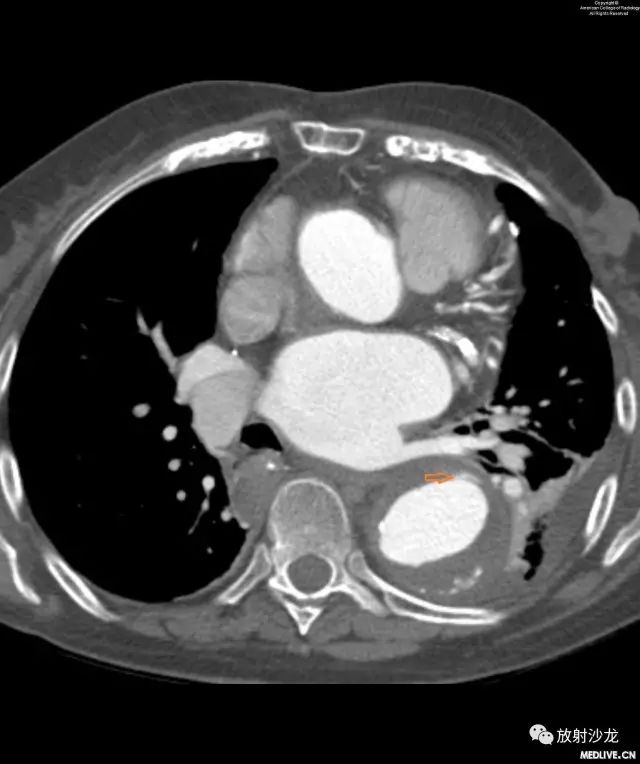

图5和图6:患者5天后由于胸痛复发回到急诊。图5的增强CT扫描显示既往的IMH出现小撕裂口,导致内膜夹层。图6显示了在下部层面出现强化的假腔。

五天后,患者由于胸痛复发及高血压急症再次回到急诊室。CT可见以前的IMH形成了Stanford B型夹层以及新出现的左侧胸腔积液。由于症状反复发作与疾病的恶化,患者被转移到一个三级医疗中心。住院期间对该患者的血压进行控制,考虑行非急诊血管内支架置入术,并在出院后对她进行密切随访。